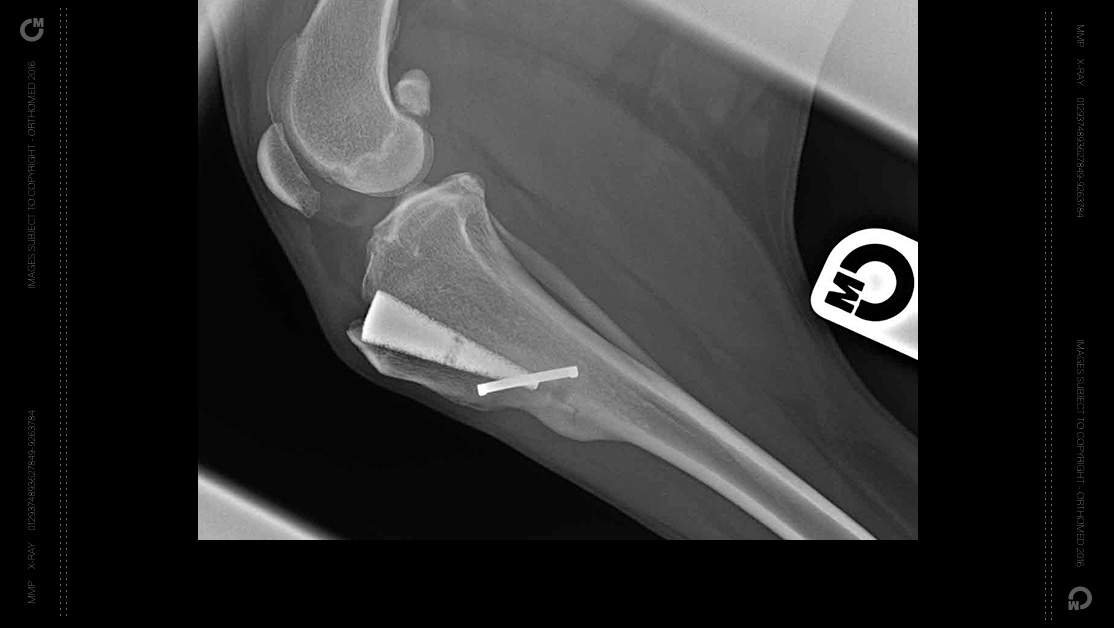

MMP uses a wedge-shaped implant of titanium OrthoFoam™ which both defines the degree of advancement of the tibial tuberosity and holds the bone in its new place while the bony ingrowth that provides permanent biomechanically robust fixation, develops.

Designed as an evolution of Tibial Tuberosity Advancement (TTA), MMP has proven itself to be a much simpler & more cost-effective procedure that has excellent outcomes.

Developed in association with the National Research Council of Canada, the biocompatible titanium OrthoFoam™ wedge paves the way for the next generation of Tibial Tuberosity Advancement (TTA).

The open porous structure and sympathetic mechanical characteristics of the titanium OrthoFoam™ implant encourages early and sustained bone ingrowth removing the need for bone grafting or similar.

New bone cells proliferate throughout the wedge, bonding it to the host bone creating a solid repair which considerably reduces convalescence and considerably improves the long term prognosis for the patient.